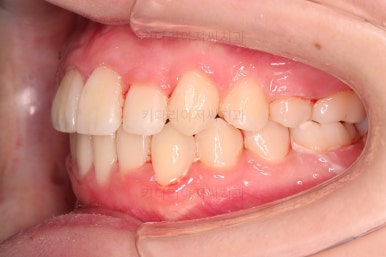

부산교정치료 초진 시 입안의 모습입니다.

치아가 전반적으로 삐뚤고, 덧니가 두드러져 보이네요.

그리고 선을 그려놨는데 윗니의 라인과 아랫니의 라인이 평행이 아니죠.

기울어 있어서 양측의 교합의 강도가 다른 상황이었습니다.